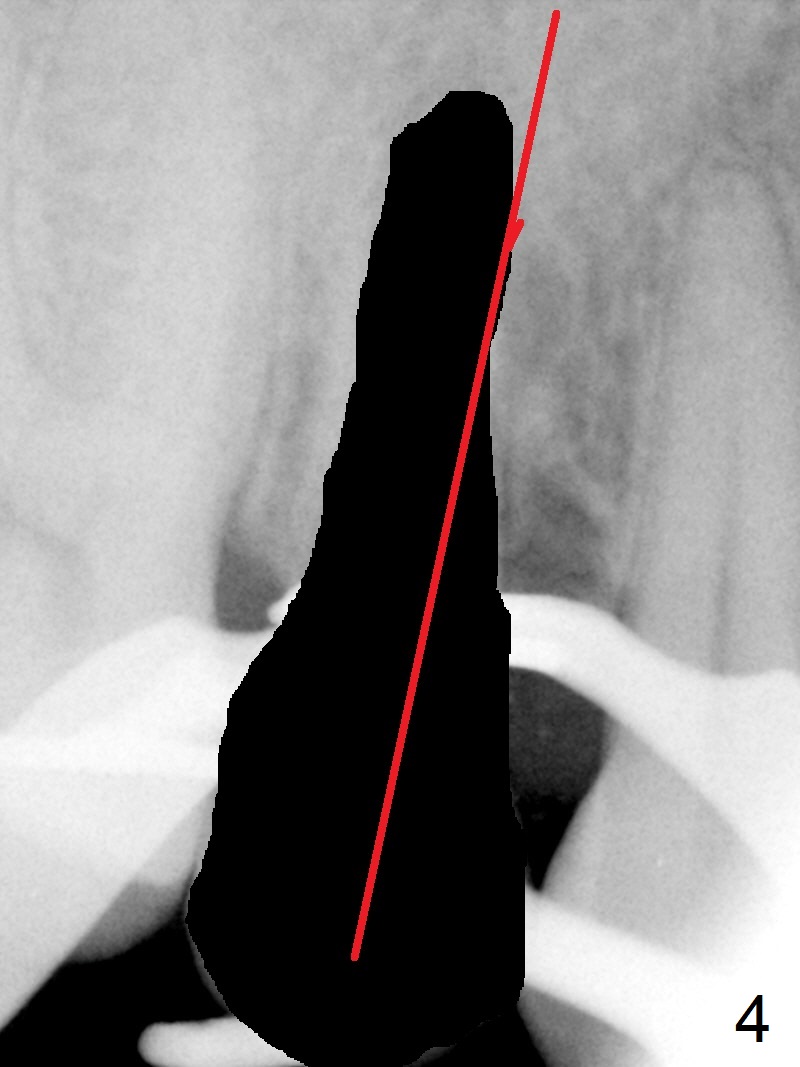

Seven years post RCT (Fig.1), the tooth #4 of a 65-year-old woman fractures subgingival palatally (Fig.2). Since the root of the affected tooth is close to the tooth #3, osteotomy is established in the mesial slope of the socket (Fig.3). Change the trajectory once the drill has penetrated the lamina dura of the socket (Fig.4). The initial depth will be 20 mm for a 3.8x16 mm implant (Fig.5).